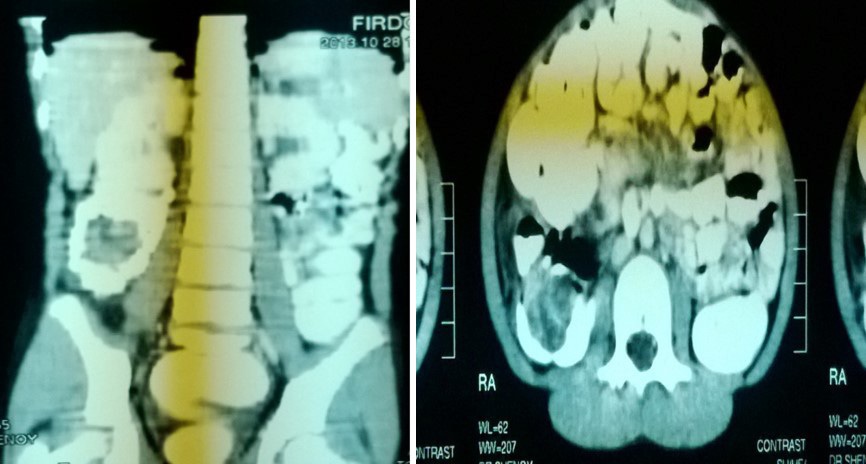

Computer tomograpahy:

• CT was done in 2 of our cases

• 1 case of PEUTZ JEGHERS SYNDROME

• 1 case was of chronic intussusception with benign polyp as lead point in ascending colon

Chronic intussusception:

• 12 years old female patient presented with chronic abdominal pain since 6 months.

• USG ABDOMEN-WNL.

• CT ABDOMEN.

• Abdominal CT scan

• Accuracy approaching 100%; especially good for lead points

• High cost, risk of radiation, and risk of sedation in children make it unpractical